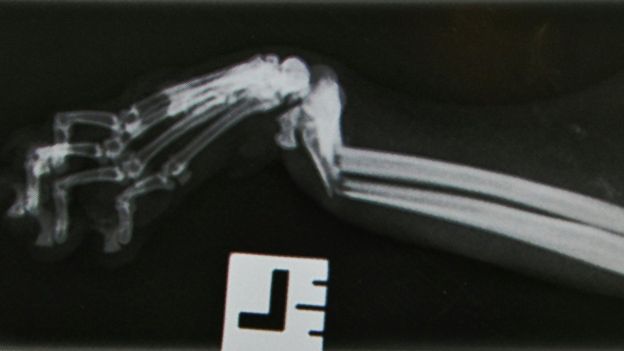

He added: “Shinji’s x-rays showed clear breaks and his surgery was complex because of where the bone had fractured, but he had a lot of fighting spirit. Just 24 hours after the operation he was up on his feet again, albeit with the external fixators holding his broken bones in place.”